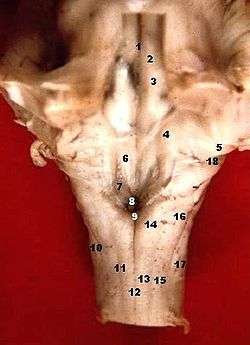

Human caudal brainstem posterior view (Colliculus facialis is #3) | |